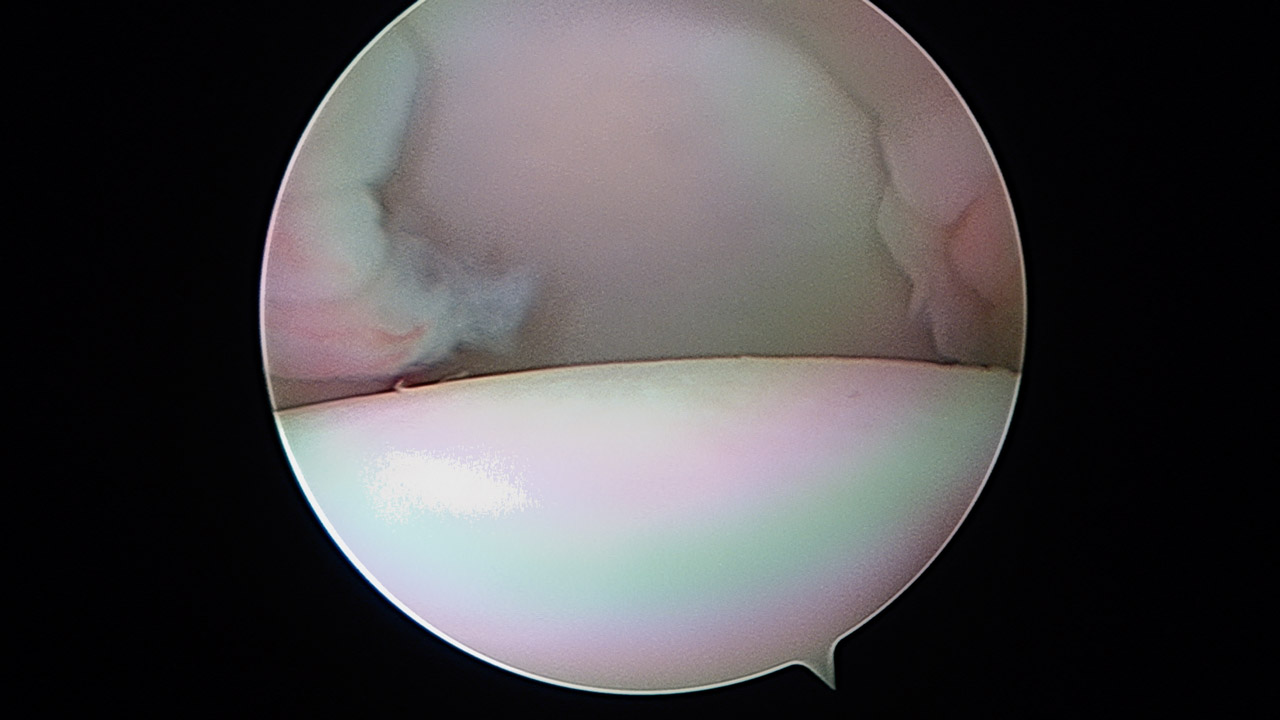

Presentamos una técnica quirúrgica artroscópica para los casos de inestabilidad traumática o atraumática de hombro, con hiperlaxitud multidireccional asociada, en los que hayan fracasado los tratamientos conservadores u otras técnicas quirúrgicas de plicatura capsular, y no presenten déficit óseo importante. Consiste en la plicatura del ligamento glenohumeral inferior (anteroinferior y posteroinferior) y la realización de una ligamentoplastia de refuerzo anterior artroscópica con aloinjerto en disposición transubescapular.

We present an arthroscopic surgical technique for cases of traumatic instability or atraumatic of the shoulder, with associated multidirectional hyperlaxity in which conservative treatments have failed, or other surgical techniques of plication capsular, and do not present major bone deficits. It consists of the plication of the lower glenohumeral ligament (anteroinferior and posteroinferior) and the accomplishment of an arthroscopic anterior reinforcement ligamentoplasty with allograft in a trans-scapular arrangement.